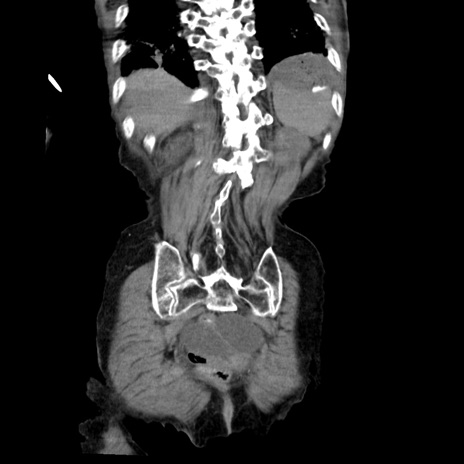

横断像

【症例】80歳代女性

【主訴】嘔吐、腹痛

【現病歴】数時間前より嘔吐あり。心窩部痛出現し、徐々に右下腹痛あり。その後も数回嘔吐あり救急搬送となる。

【身体所見】腹部は膨隆しているが軟らかく圧痛なし。腸雑音はやや亢進。

【データ】WBC 12000、CRP 19.05